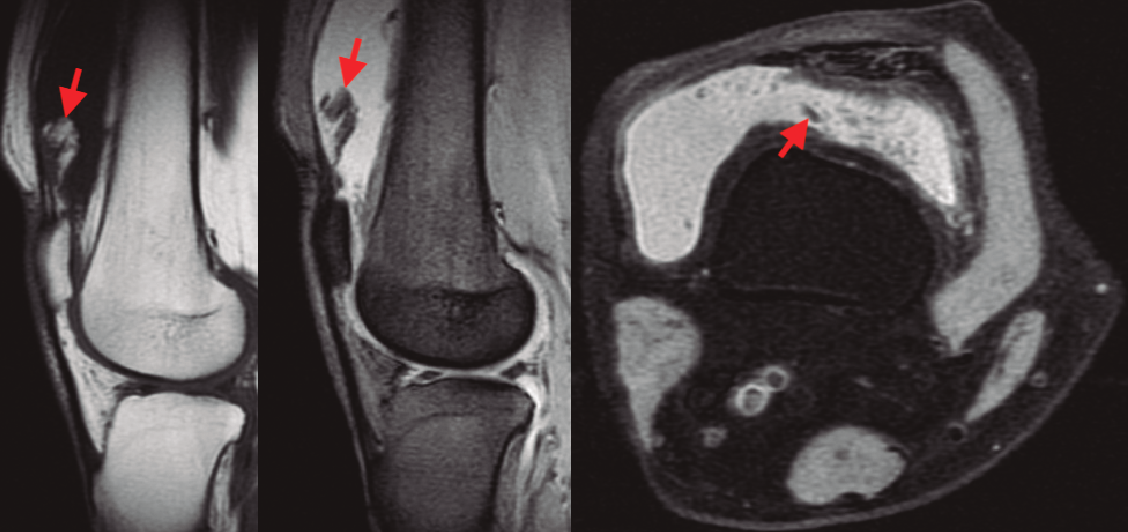

En la resonancia magnética (RM) de los hombros, los citados cambios degenerativos con ­quistes subcondrales en la cabeza humeral y presencia de cambios inflamatorios en cabeza y troquíter eran evidentes, observándose el LA como una infiltración grasa con vellosidades en la cavidad articular hiperintensas en T1 y T2, con imágenes hipointensas en las ventanas STIR y supresión grasa. También se observó el acúmulo de líquido en la zona de la bursa subacromial (Figura 1), presentando en ocasiones una discreta migración proximal de la cabeza humeral. En ocasiones se evidenció también una alteración de la señal en los tendones del manguito rotador, compatibles en algún caso con roturas. En la RM de los casos de rodilla se evidenció el LA como un crecimiento de partes blandas en la bursa suprapatelar de intensidad compatible con la grasa, asociada a la presencia de derrame articular (Figura 2). Dicha masa era heterogénea, irregular, adherida al plano anterior.

Figura 2. Imágenes en corte sagital y axial de las ventanas T1, T2 y supresión grasa de la RM, evidenciando una masa vellosa en el receso suprapatelar con intensidad de señal grasa, (señaladas mediante flechas), asociada a un derrame articular.